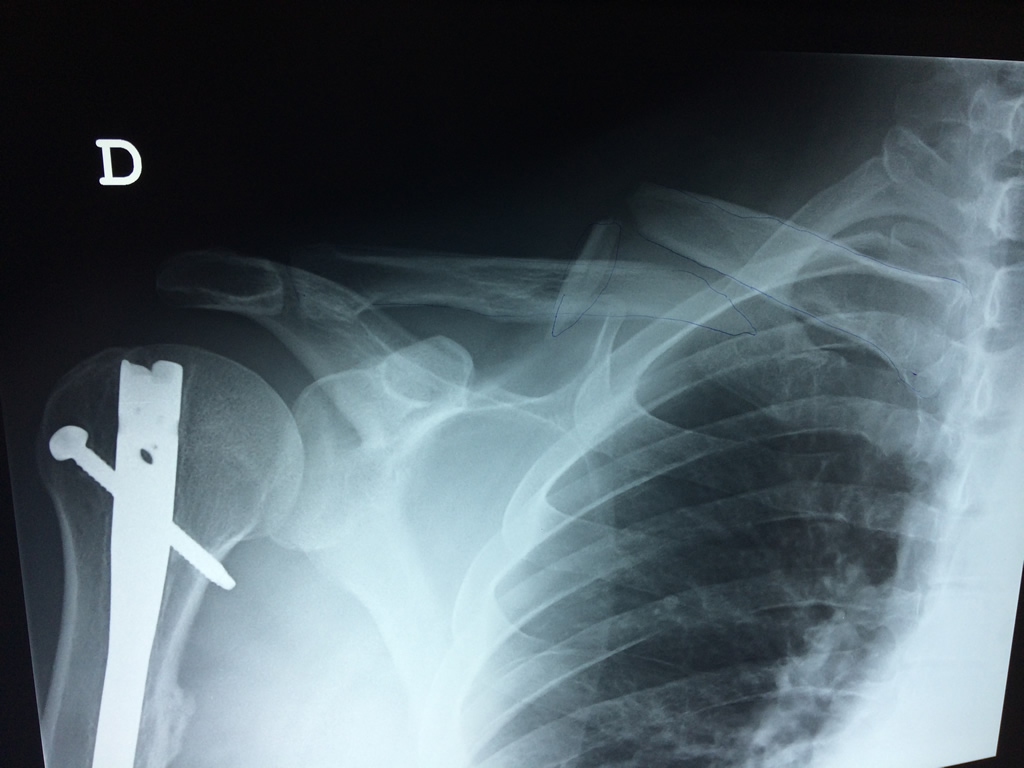

Cirugía de Fémur - Clavícula

La clavícula es un hueso largo, con forma de "S" itálica, situado en la parte anterosuperior del tórax. Junto con la escápula forman la cintura escapular. Se puede palpar por toda su longitud y se extiende del esternón al acromion de la escápula, siguiendo una dirección oblicua lateral y posterior.